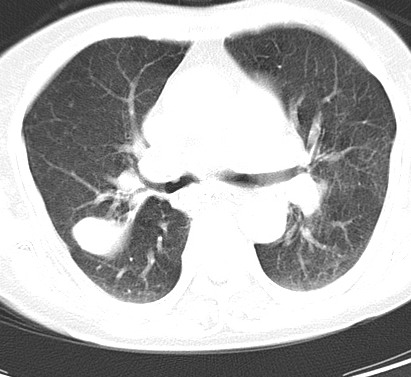

以下是引用hhcckk在2007-3-2 14:51:00的发言:[br]考虑结核球可能性大,依据[br]1病灶在下叶背段,结核的好发部位[br]2病灶内有大量的钙化,纵隔内有大量的淋巴结钙化[br]3重要的是半年前与现在相比无变化,假如是肿瘤的话不会这么‘善良’[br]4病灶周围卫星灶不明显,病灶有毛刺,胸膜凹陷,肿瘤不能完全排除,有条件的话最好做个活检

以下是引用liuyue在2007-3-2 17:15:00的发言:[br]1位置:右上叶后段[br]2性质:大分叶、粗长毛刺、条状斑片状钙化、纵隔多发淋巴结钙化,无强化,故考虑:肺结核灶(陈旧)